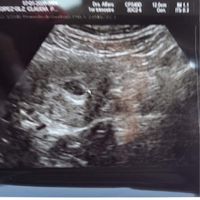

Hola hermosas brides Hoy vengo a contarles lo que he pasado en estas dos semanas. Bueno pues les conté como le había dado la noticia a mi esposo y después de eso luego luego a hacer cita con mi gine...

Hola chicas así como lo dice el tema estoy embarazada, me hice una prueba de orina y rapidísimo marco creo tener 3 o 4 semanas pero el martes iré a mi primera cita y eco. Estoy feliz y muy nerviosa...